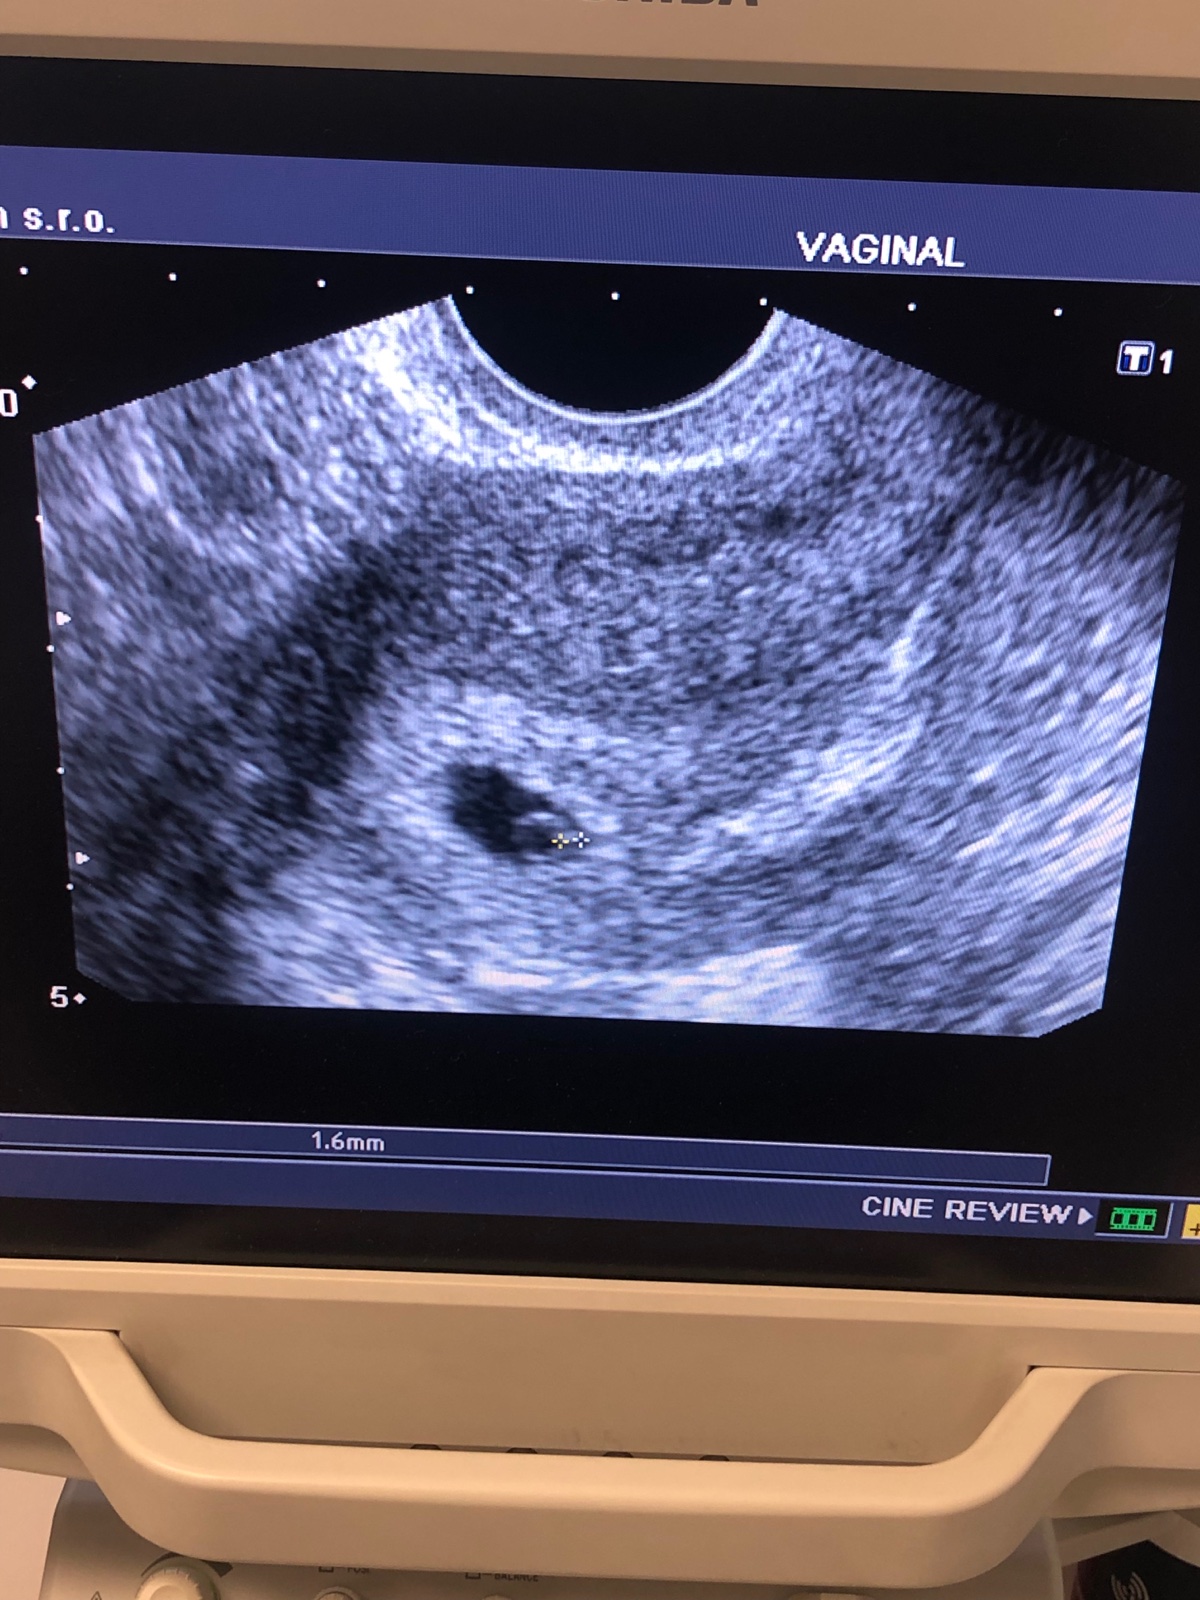

Dnes som ocikala dalsi a toto

Neviem co si mam mysliet